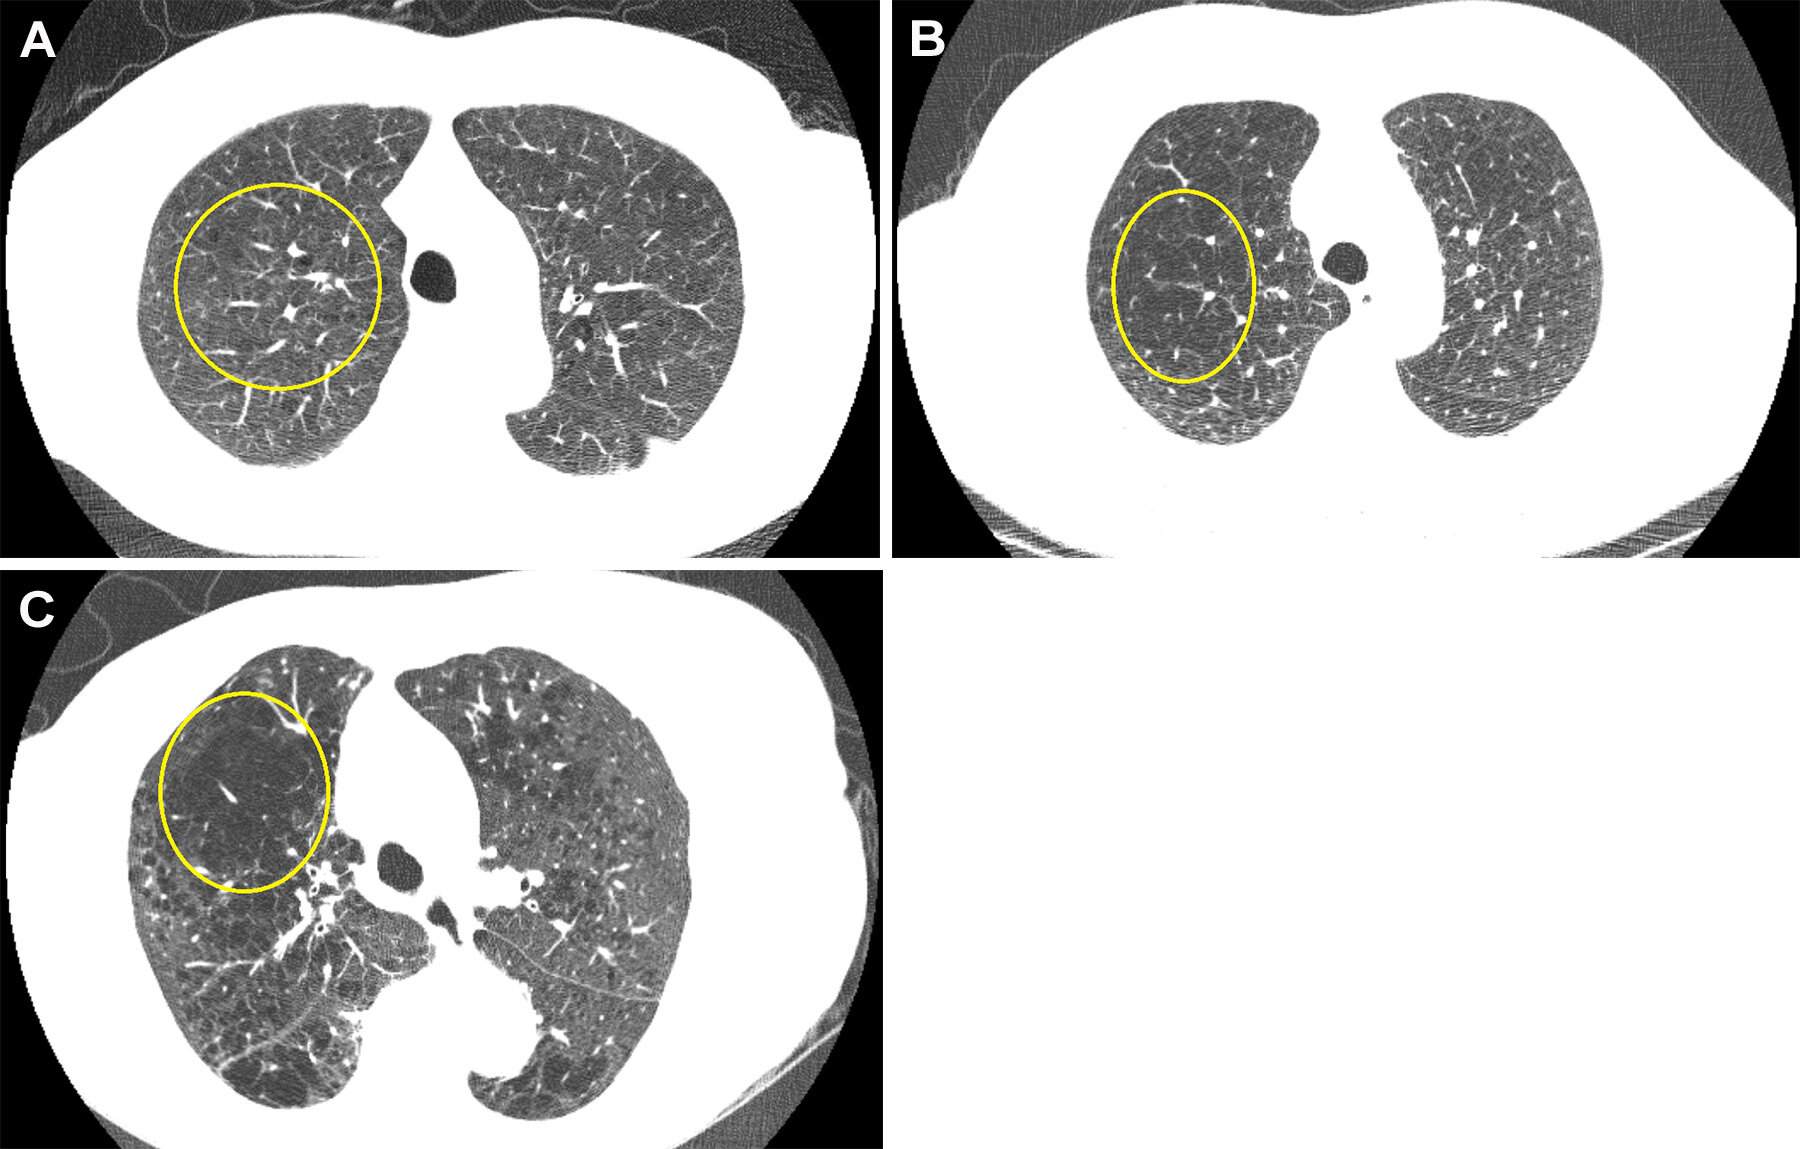

Un radiologue thoracique expérimenté a évalué chaque LDCT et a attribué un score reflétant le niveau d’emphysème présent de 0 (aucun) à 3 (sévère).

Parmi les participants de l’étude, 70,9% n’avaient aucune preuve d’emphysème. Le pourcentage d’emphysème léger, modéré et sévère était respectivement de 21,1%, 5,7% et 2,4%. Près de 80% des participants identifiés à l’emphysème sur leur LDCT de base n’avaient pas été diagnostiqués auparavant, dont 5% des participants avec un emphysème modéré ou sévère.